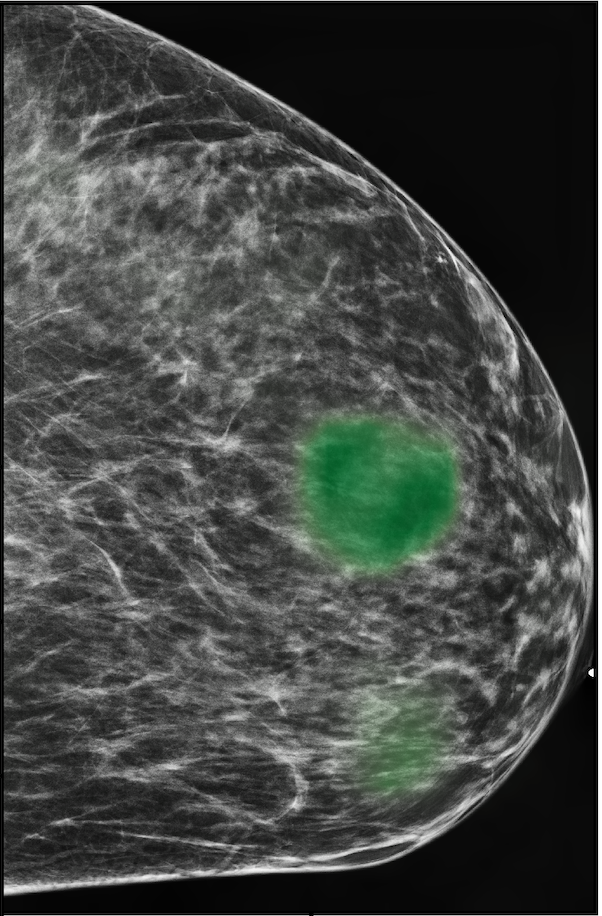

The NYU Breast Cancer Screening Dataset [78] includes 229,426 exams (1,001,093 images) from 141,472 patients.222Our retrospective study was approved by our institutional review board and was compliant with the Health Insurance Portability and Accountability Act. Informed consent was waived. Each exam contains at least four images which correspond to the four standard views used in screening mammography: R-CC (right craniocaudal), L-CC (left craniocaudal), R-MLO (right mediolateral oblique) and L-MLO (left mediolateral oblique). An example is shown in Figure 3.

Across the entire dataset (458,852 breasts), malignant findings were present in 985 breasts () and benign findings in 5,556 breasts (). All findings are confirmed by at least one biopsy performed within 120 days of the screening mammogram. For the remaining screening exams that were not matched with a biopsy, we assigned labels corresponding to the absence of malignant and benign findings in both breasts. In each exam, the two views of the same breast share the same label.

For all exams matched with biopsies, we asked a group of radiologists (provided with the corresponding pathology reports) to retrospectively indicate the location of the biopsied lesions. This way we obtained the segmentation labels: where if pixel belongs to the benign/malignant findings. An example of such a segmentation is shown in Figure 3. In all experiments (except for experiments in Section 3.6 that assess the benefits of utilizing segmentation labels), segmentation labels are only used for evaluation. We found that, according to the radiologists, approximately of exams were mammographically occult, i.e., the lesions that were biopsied were not visible on mammography, even retrospectively, and were identified using other imaging modalities: ultrasound or MRI.